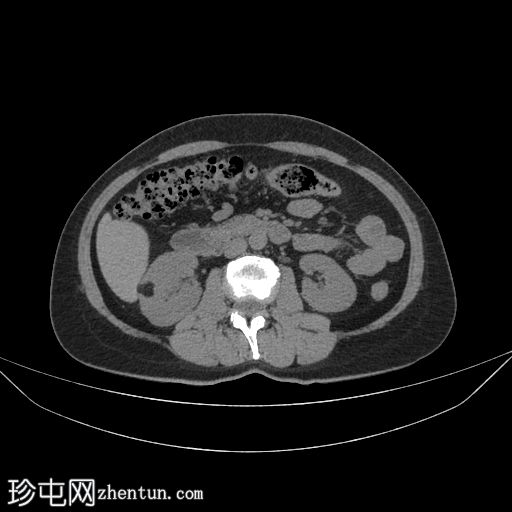

轴位增强CT(门静脉期)

在这张平扫和增强CT图像中,我们可以看到右肾内有一处脂肪衰减病灶,未见并发症或其他显著异常。

肾血管平滑肌脂肪瘤是

肾脏

脂肪

性病

变最常见的病因。出血风险与血管丰富程度和瘤内动脉瘤的存在相关。本次发现为偶然发现;除非出血,否则腹痛并非肾血管平滑肌脂肪瘤的常见临床表现。